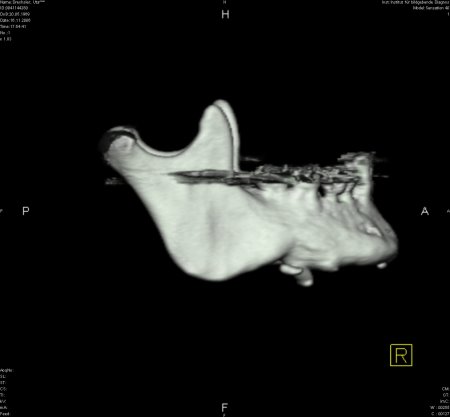

Zur genauen Planung der Kieferkorrektur wurde ich zum CT geschickt. Aus den scheibchenweisen Bildern setzte der Computer ein dreidimensionales Bild zusammen. Dabei ist auch sehr deutlich dieses verlagerte Knochenstück zu sehen.

Zwischenzeitlich stand auch mal die Überlegung im Raum, eine Kinnplastik durchzuführen, bei der die Kinnspitze abgesägt und danach im "richtigen" Winkel wieder aufgesetzt wird. Das klang natürlich auch erst mal ein bissel erschreckend - aber schließlich zählt das Ergebnis. Nach Auswertung der 3-D-Annimation wurde dann allerdings "nur" die erstbeschriebene Kieferkorrektur durchgeführt.